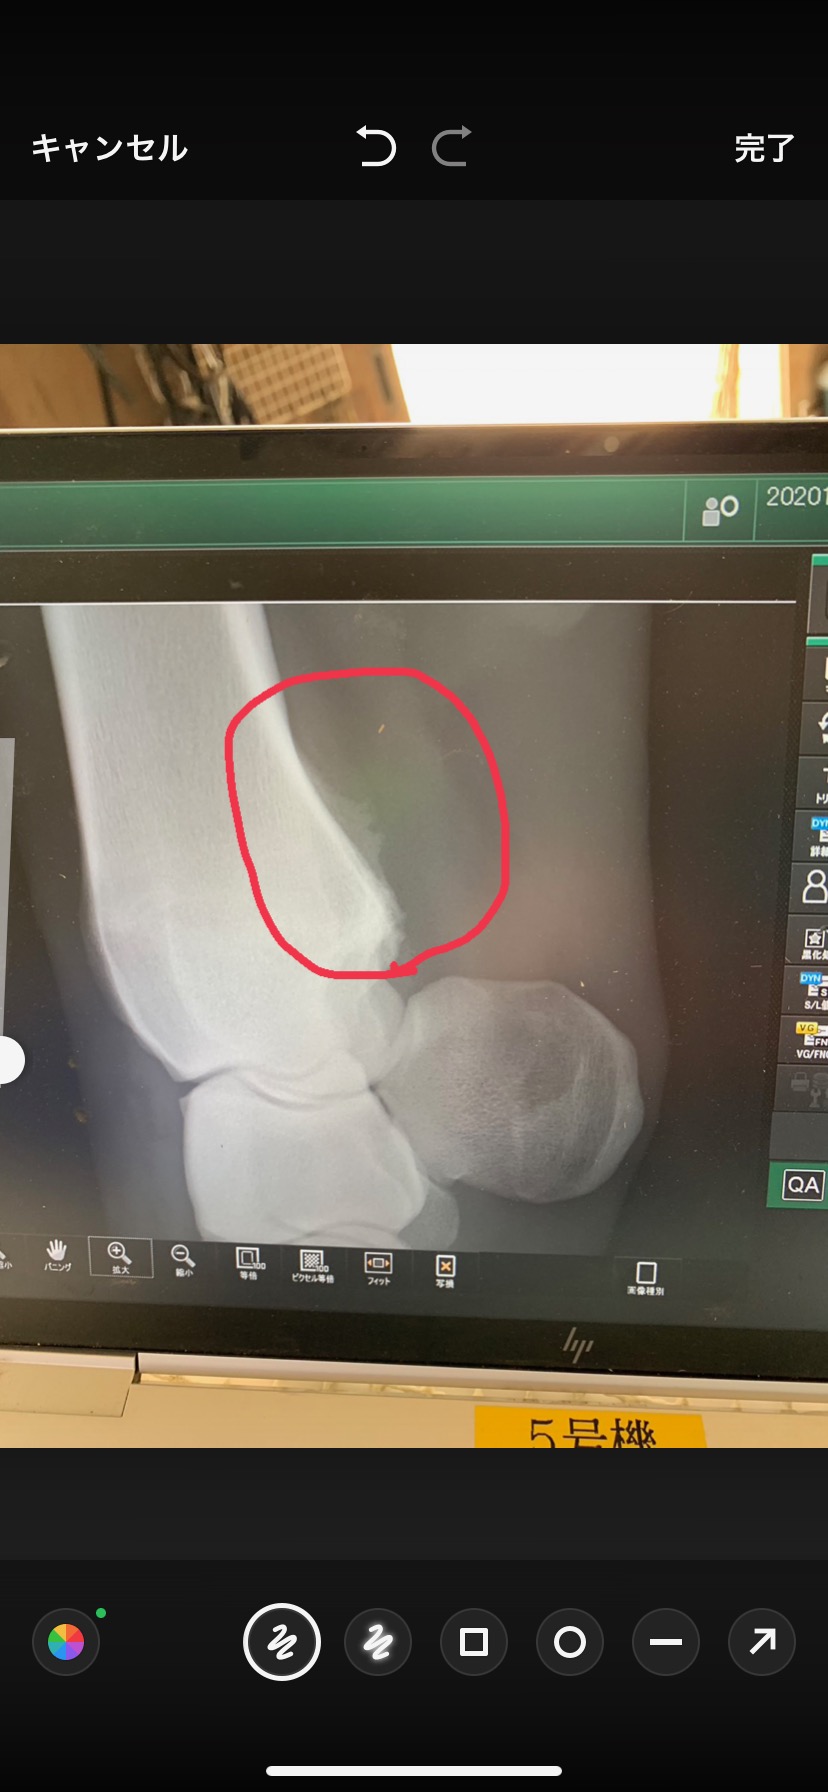

この一戦のあと、左前のひざに骨膜炎が判明(添付の画像をご確認ください)したことあり、2戦のみでのオークション出品となります。成長が遅いと感じるところはありますが、調教の動きなどから素質は感じますし、将来性は十分に秘めていると思います。競馬でも不利があるなどまともに力は出せていませんし、今後の変わり身にご期待いただければと思います。